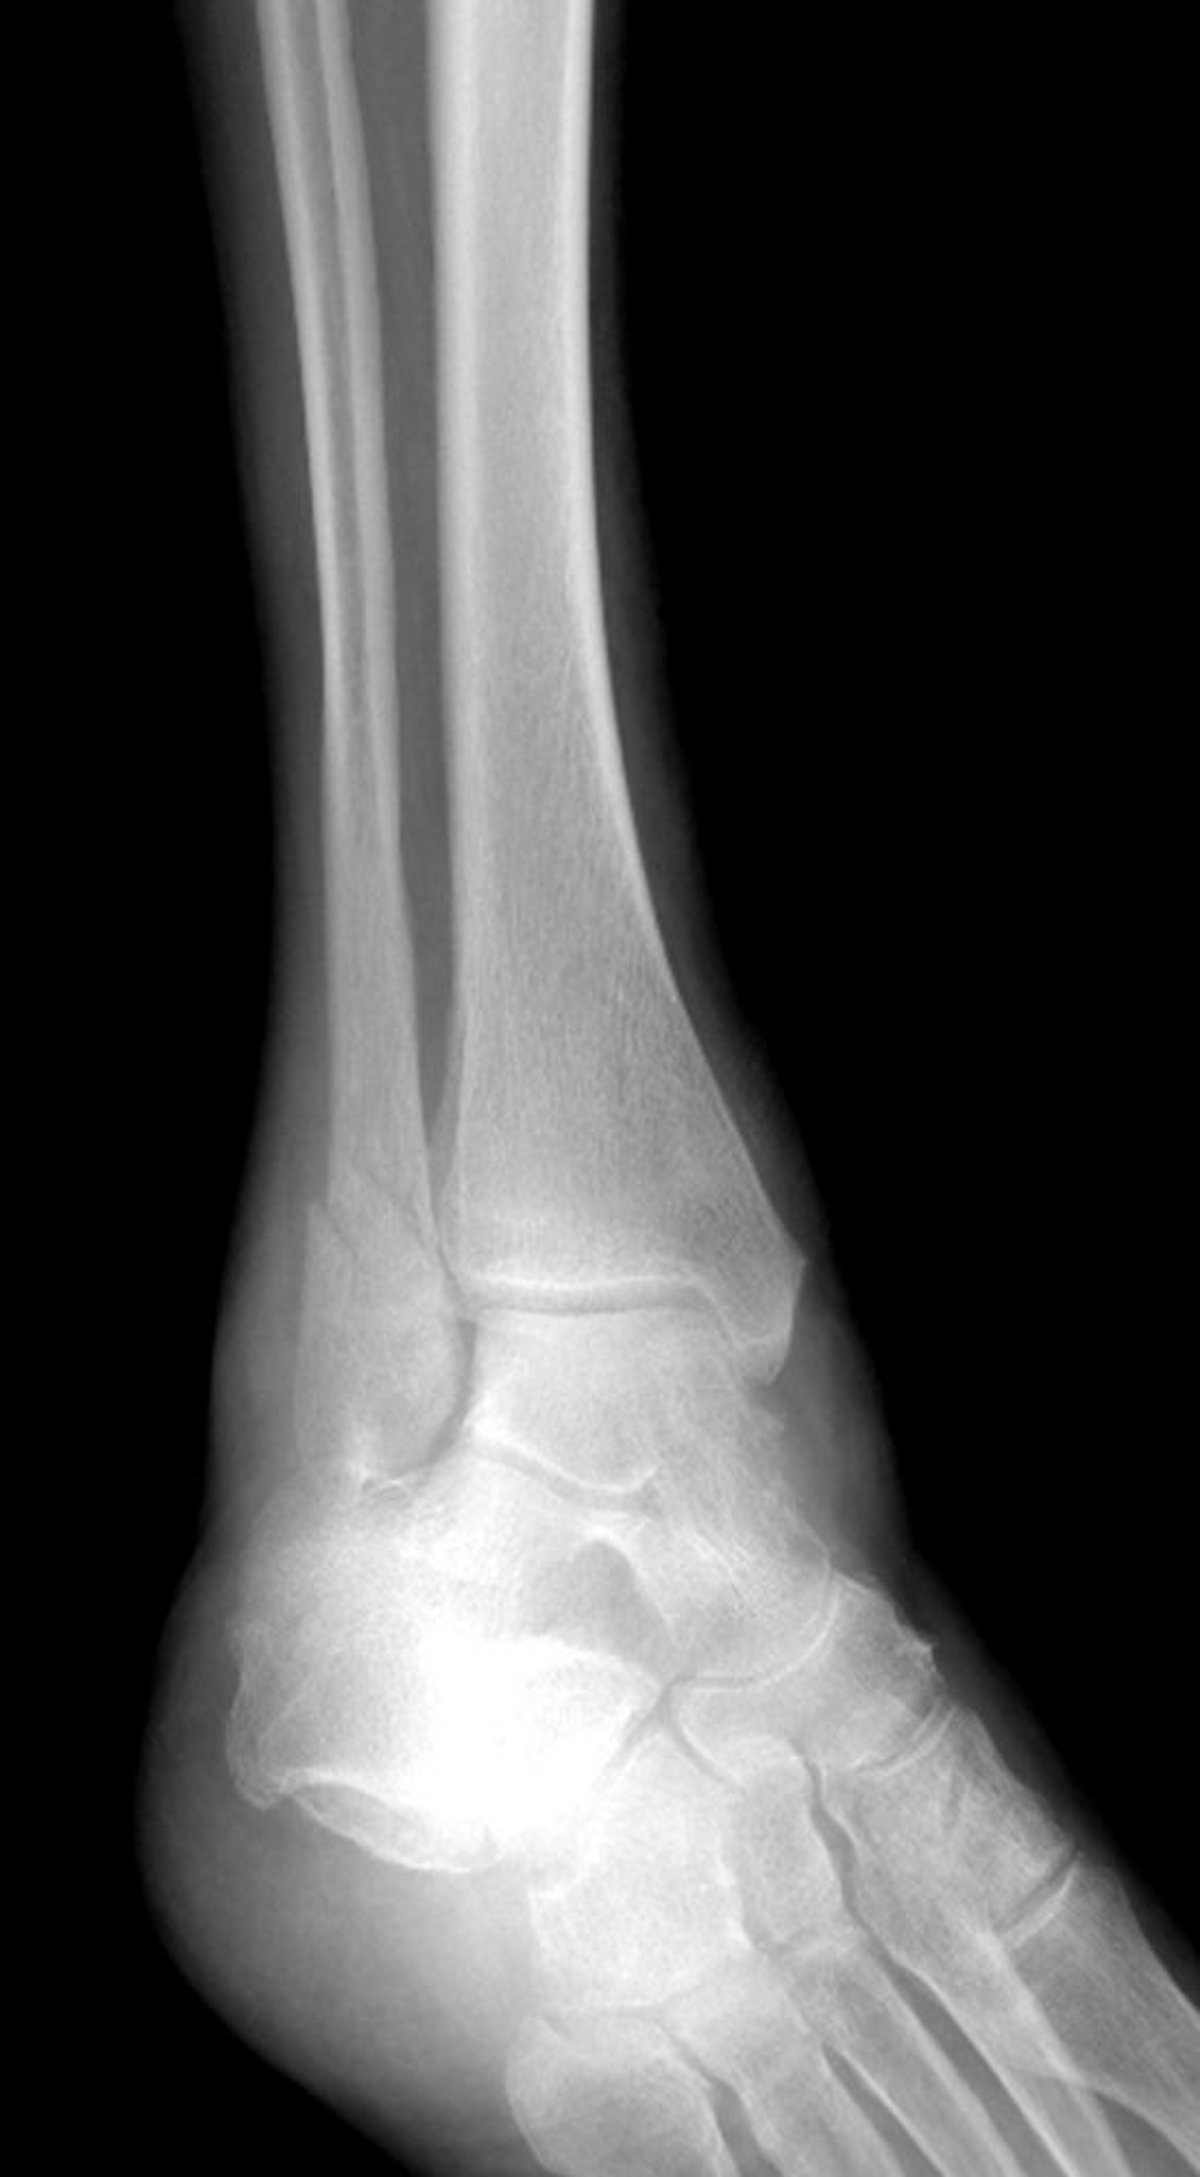

Fractura de un maléolo lateral

Esta fractura de tobillo afecta el maléolo lateral, pero respeta el maléolo medial.